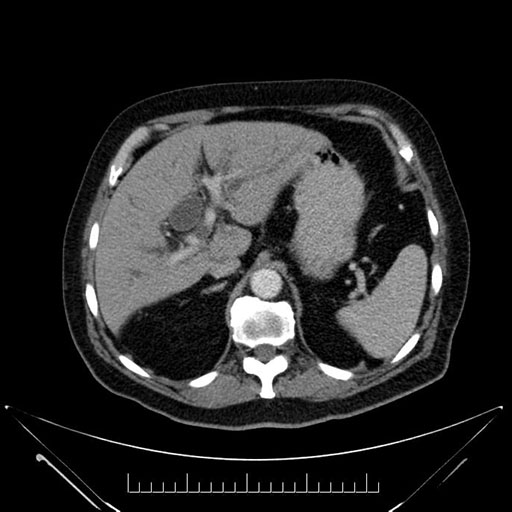

Axial - stented